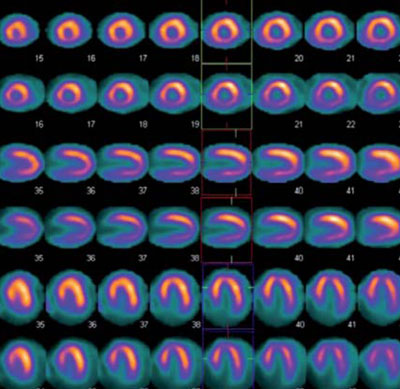

Paciente masculino de 75 años, sin antecedentes de cardiopatía, hipertenso, dislipidémico e hipotiroideo, con cuadro de disnea progresiva. En el ECG se observa ritmo sinusal de 63 cpm, P y PR normales, con bloqueo completo de rama derecha, hemibloqueo anterior izquierdo y alteraciones difusas de repolarización, sin minivoltajes (Figura 1). El eco Doppler mostró severo engrosamiento del VI, hipocontractilidad global más marcada en pared anterior, fracción de eyección del ventrículo izquierdo (FEVI) de 30% y disfunción diastólica severa, configurando un patrón de miocardiopatía hipertrófica (Figura 2). Con este resultado se realiza RM que informa, en secuencia de RT, imposibilidad de anulación del miocardio con diferentes tiempos de inversión, compatible con la presencia de amiloidosis. Presenta además RT del VD, con QALE score de 12 (Figura 3). Dada la disnea aparentemente desproporcionada, se realiza centellograma de perfusión miocárdica con 99mTc-sestamibi con estrés farmacológico para descartar componente isqué mico, que no demuestra alteraciones de la perfusión y FEVI <50% (Figura 4).

Figura 4: Estudio de perfusión miocárdica con 99mTc-sestamibi, estrés farmacológico con dipiridamol (línea superior) y reposo (línea inferior), el cual no evidencia zonas de hipoperfusión.